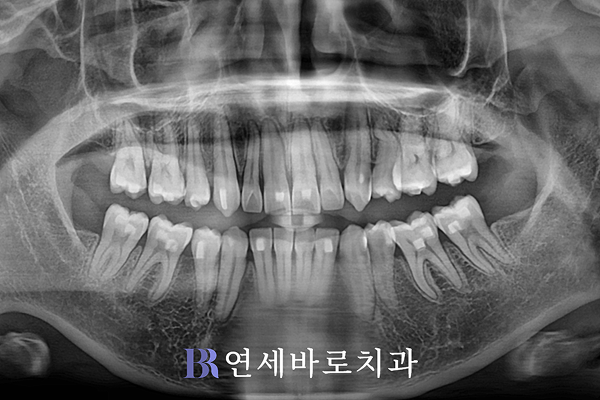

인비절라인 발치교정이

어느 정도 마무리되었습니다.

영구치를 제거한 공간이

조금씩 폐쇄되기 시작했네요.

발치교정이 아주 순조롭게

진행되는 것으로 보였습니다.

악궁 모양도 완만해졌으며,

전체적으로 훨씬 더 이상적인

U자 아치가 형성됐는데요.

폭경이 충분히 넓어졌습니다.

한편 앞서 말씀 드린 것처럼

전치부 후방이동과 함께

앞니의 전방경사를 조절하는

교정치료가 이뤄졌는데요.

예전에 비해 치아의 각도가

상당히 감소하였습니다.

그만큼 튀어나와 있는 입도

들어가기 시작했습니다.

당시 치료가 진행 중이라

측면 교합이 아직 완벽하게

완성되지는 못했습니다.

그래도 어금니가 이전보다는

조금씩 맞춰지기 시작하는

모습이 확인되기도 했습니다.

덧니가 고르게 배열됨에 따라

잇몸라인도 균일해졌으며,

어긋나 있던 중심선 불일치도

상당히 호전되었습니다.